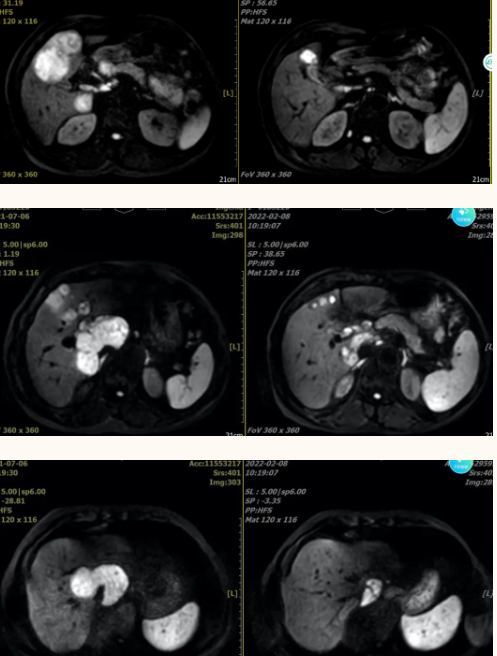

该院肝胆外科、肿瘤内科、影像科、放疗科等专家经过MDT(多学科联合会诊),认真研究了王大叔病情后,告知可以先转化治疗,观察治疗效果再考虑手术切除,王大叔重新点燃了生命的希望。据该院副院长、肝胆外科主任医师张建华介绍,转化治疗的定义,就是肿瘤经过放疗、化疗、靶向治疗、免疫治疗、介入治疗乃至中药治疗之后肿瘤缩小,使原来无法切除的肿瘤变成能达到R0切除的过程,称为转化治疗成功,而R0切除的意思就是肿瘤能达到病理情况下完整切除。这有望大大延长患者的无进展生存期以及总的生存期,使患者的生活质量得到提高。于是,该院肝胆外科从2020年7月7日开始,为王大叔进行转化治疗(HAIC+免疫治疗),至2022年1月11日,转化治疗效果明显,左半肝肿瘤由原来的8.99×8.44厘米缩小到1.9x2.7厘米,尾叶肿瘤由原来的9.38x6.19厘米缩小的到5.2×3.9厘米。2022年2月17日,经MDT专家再次评估肿瘤回缩可切除,于是行“左半肝切除+全尾状叶切除+肝S6段肿瘤切除+门静脉切开取栓术+肝门部淋巴结清扫术”。在张建华副院长的主持下,历经8个小时,手术获得成功。手术难点,就是肿瘤紧紧包裹下腔静脉,术中两条大血管极易破裂导致患者大出血死亡,手术难度,相当于肝移植。患者手术12天后出院,病理报告提示:肿瘤切缘阴性,达到R0切除。2022年3月16日返院复查,各项指标已趋正常,未发现转移复发。